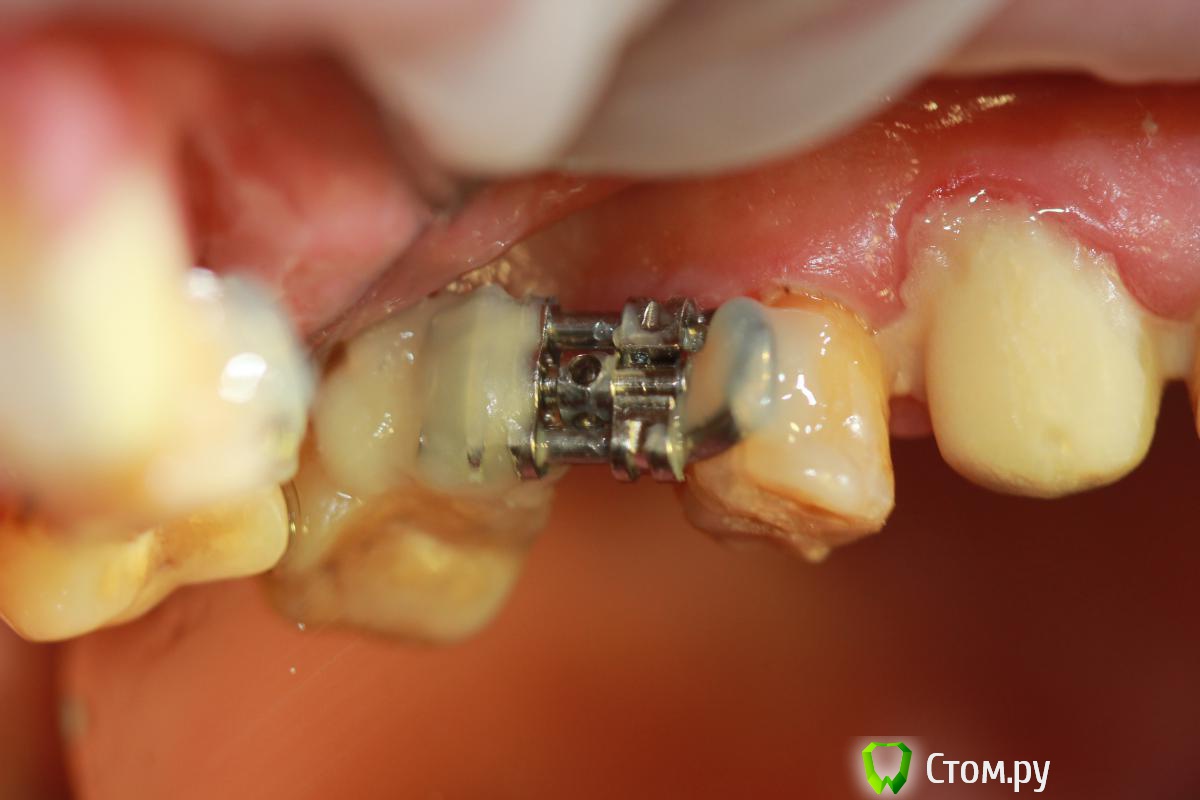

Ibulat_1986 Опубликовано 16 декабря, 2013 Поделиться Опубликовано 16 декабря, 2013 я не ортодонт, но недавно наткнулся на следующее.допускается ли такая конструкция для дистализации моляров? Ссылка на комментарий

Ibulat_1986 Опубликовано 16 декабря, 2013 Поделиться Опубликовано 16 декабря, 2013 погуглил - больше похоже на винт Бертони для пластинок. Ссылка на комментарий

Ayrat_zub Опубликовано 16 декабря, 2013 Поделиться Опубликовано 16 декабря, 2013 я не ортодонт, но недавно наткнулся на следующее.допускается ли такая конструкция для дистализации моляров?Жесть)) никогда такого не встречал) но оптыта не так много) похожие аппраты есть(более эргономичные), но эта версия удивила)) если опора контролируется, то наверное допускается))) 1 Ссылка на комментарий

Ibulat_1986 Опубликовано 16 декабря, 2013 Поделиться Опубликовано 16 декабря, 2013 Жесть)) никогда такого не встречал) но оптыта не так много) похожие аппраты есть(более эргономичные), но эта версия удивила)) если опора контролируется, то наверное допускается))) этот пациент все равно будет в клинике появляться. посмотрим. по возможности буду фотографировать Ссылка на комментарий

LeFor Опубликовано 18 декабря, 2013 Поделиться Опубликовано 18 декабря, 2013 я не ортодонт, но недавно наткнулся на следующее.допускается ли такая конструкция для дистализации моляров?вот это полный писец! походу пластиночный ортодонт решил подзаработать))) Ссылка на комментарий

LeFor Опубликовано 18 декабря, 2013 Поделиться Опубликовано 18 декабря, 2013 насчет громоздких конструкций- смотря какой пациент... как то делал вот так...на втором снимке вверху опора на дентальный имплант- эксперимент))) 5 Ссылка на комментарий

Ibulat_1986 Опубликовано 20 декабря, 2013 Поделиться Опубликовано 20 декабря, 2013 насчет громоздких конструкций- смотря какой пациент... как то делал вот так...на втором снимке вверху опора на дентальный имплант- эксперимент)))нормально! особенно порадовал первый снимок! класс Ссылка на комментарий